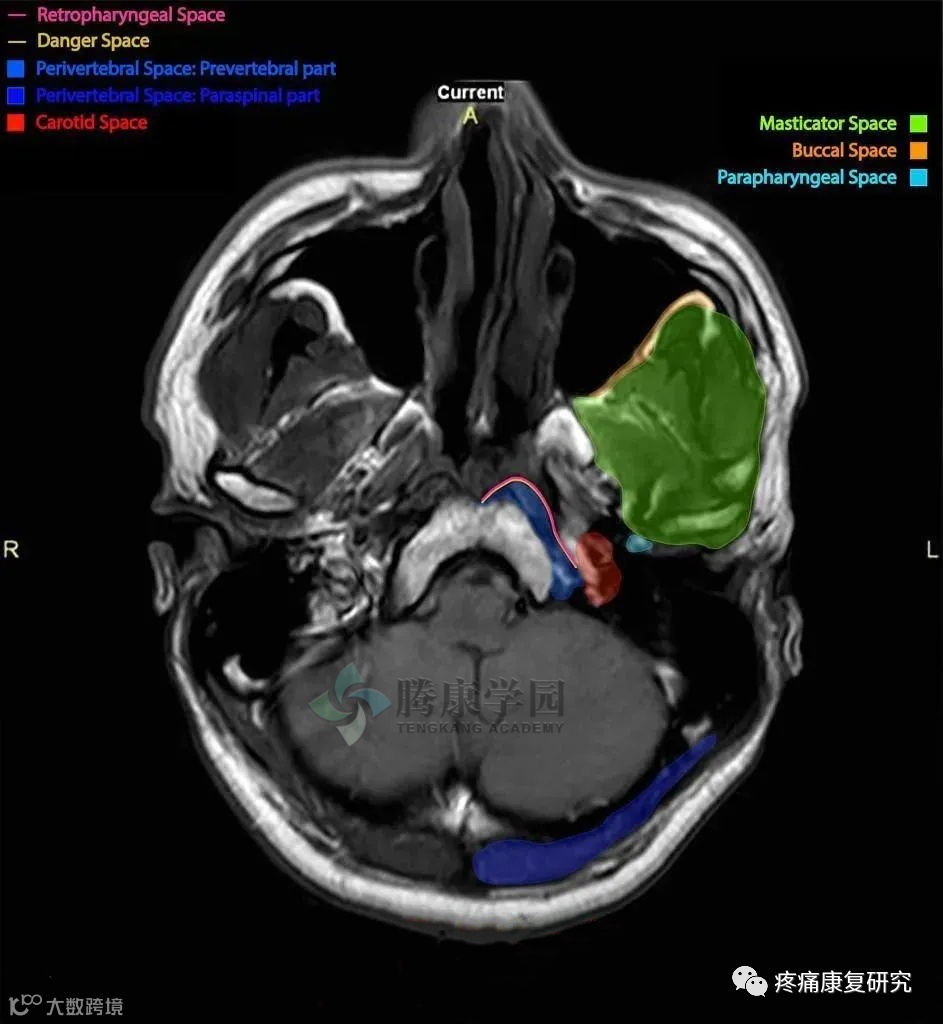

Guidera 等总结了头颈部筋膜的层次和间隙,每个筋膜和间隔都有其上下延伸,颅底筋膜分隔出如下 6 个颈深间隙: 下颌下间隙、咽旁隙、颈鞘间隙、内脏间隙、咽后间隙、危险间隙以及椎前间隙。

Masticator Space:咀嚼肌间隙;Buccal Space:颊间隙;Parapharyngeal Space:咽旁间隙;Retropharyngeal Space:咽后间隙;Danger Space:危险间隙;Perivertebral Space: Prevertebral part:椎周间隙-椎前部分;Perivertebral Space: Paraspinal part:椎周间隙-椎旁部分;Carotid Space:颈动脉间隙

这些对颅底筋膜层次及筋膜间隙的认识,界定了颅底腹侧面重要结构之间的分界,有助于临床对于颅底解剖层次的认识、感染等病变蔓延的理解和手术中解剖标志的辨认。